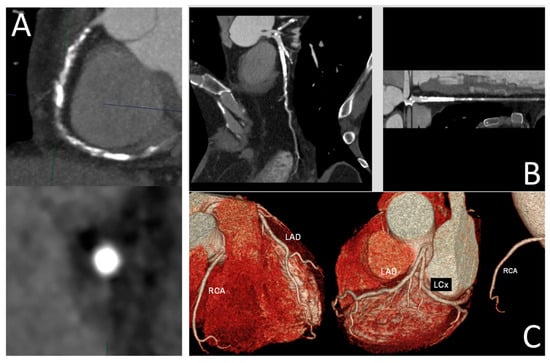

Figure 3. Optimizing treatment decisions with FFR-CT: (Left): A curved multiplanar reformatted coronary CTA image in a 64-year-old man with stable chest pain reveals severe stenoses in the mid left anterior descending (LAD) artery and distal right coronary artery. (Right): The corresponding FFR-CT image shows a value of 0.51 measured 2 cm distal to the lesion, indicating severely reduced flow. Based on these findings, the patient proceeded to invasive coronary angiography, followed by intervention. Please refer to Figure 4’s caption for the degree of stenosis in relation to different colors. Reprinted with permission under open access from Kasaeian et al. [6].

Kasaeian et al. reviewed the clinical applications of FFR-CT in coronary artery disease [6]. FFR-CT has been increasingly reported in the literature to yield improved accuracy in guiding patient management compared to standard coronary CT angiography (CTA). Real-world evidence of using FFR-CT in clinical practice has been validated by a number of multicenter trials proving that FFR-CT serves as a gatekeeper to invasive coronary angiography by reducing a significant number of unnecessary invasive procedures (Figure 2 and Figure 3). FFR-CT is associated with significantly lower all-cause mortality, so it can guide confidential clinical decision-making. Judicious use of FFR-CT to guide coronary CTA interpretation was discussed alongside distal-to-lesion FFR-CT measurement, showing improved concordance with invasive FFR, hence further enhancing diagnostic precision. In this study, the limitations of FFR-CT are highlighted, along with the impact of high-quality coronary CTA image acquisition and coronary calcium scores on FFR-CT performance. Future potential applications of FFR-CT, such as its implementation in the evaluation of coronary artery anomalies (Figure 4) and plaque characterization, are also reviewed. These authors also reviewed the role of FFR-CT as a reliable tool to plan percutaneous coronary intervention (PCI) and identify suitable patients undergoing coronary artery bypass grafting. Finally, they summarized the role of FFR-CT combined with risk stratification as a gatekeeper to the catheterization lab to reduce unnecessary invasive procedures without comprising clinical outcomes.